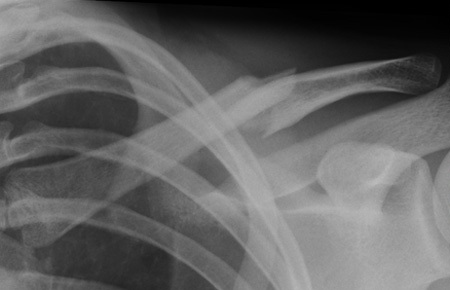

Mastering the Management of Scaphoid Fractures: Avoid Complications

- Scaphoid Fracture: Accurate Diagnosis & Best Treatment Options

- Scaphoid Fractures: Advanced Clinical Guide to Anatomy, Biomechanics, & Management

- Mastering Carpal Fracture Fixation: An Intraoperative Guide to Non-Scaphoid Injuries